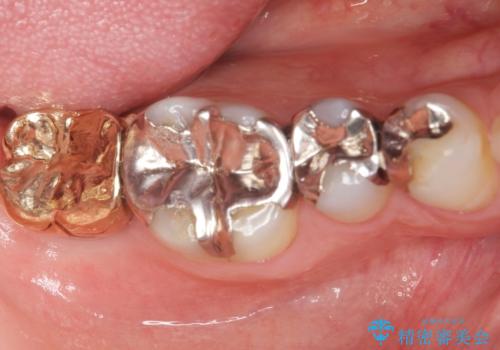

患者様のご希望によりPGA(金白金合金)クラウンによる補綴を行いました。

「金歯は咬み心地もいいし、見た目もカッコイイ!」と喜んで下さいました。

自然な使用感にご満足頂き、他の部位もPGAクラウンによる治療をご希望され現在治療中です。

クラウンの種類:PGA(Platinum Gold cast Alloy・金白金合金)クラウン